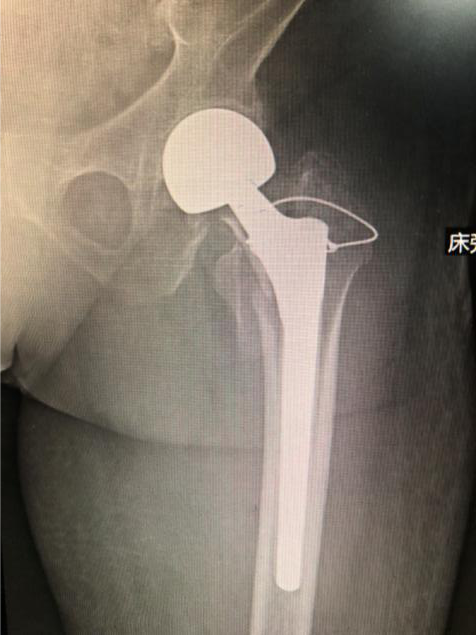

近日,西電集團醫(yī)院骨科為102歲的焦奶奶實施左側(cè)股骨頭置換術(shù),幫助老人重新下地走路。

為確保萬無一失,骨科與醫(yī)務(wù)科、麻醉科、胸外科、神經(jīng)內(nèi)科、心內(nèi)科、輸血科等多學(xué)科會診后,為焦奶奶精心制定了手術(shù)方案,張富軍主任主刀為102歲焦奶奶實施左側(cè)股骨頭置換術(shù)。

憑著骨科團隊精湛的醫(yī)術(shù)、嫻熟的手法和醫(yī)護團隊間緊密協(xié)作,順利攻克了術(shù)中各個難點,手術(shù)圓滿成功。術(shù)后下午,焦奶奶恢復(fù)情況良好,在家屬攙扶下能短暫下床行走,隨著時間的推移,焦奶奶越走越穩(wěn)。